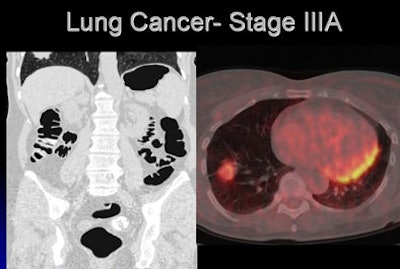

![]() |

| CT images of a 54-year-old woman revealed an opacity at the right lung base. The radiologist recommended a dedicated chest CT, which revealed abnormalities in the mediastinum; the patient subsequently underwent PET, and a biopsy confirmed lung cancer, stage IIIa. The patient was doing well following surgery, chemotherapy, and radiation. |